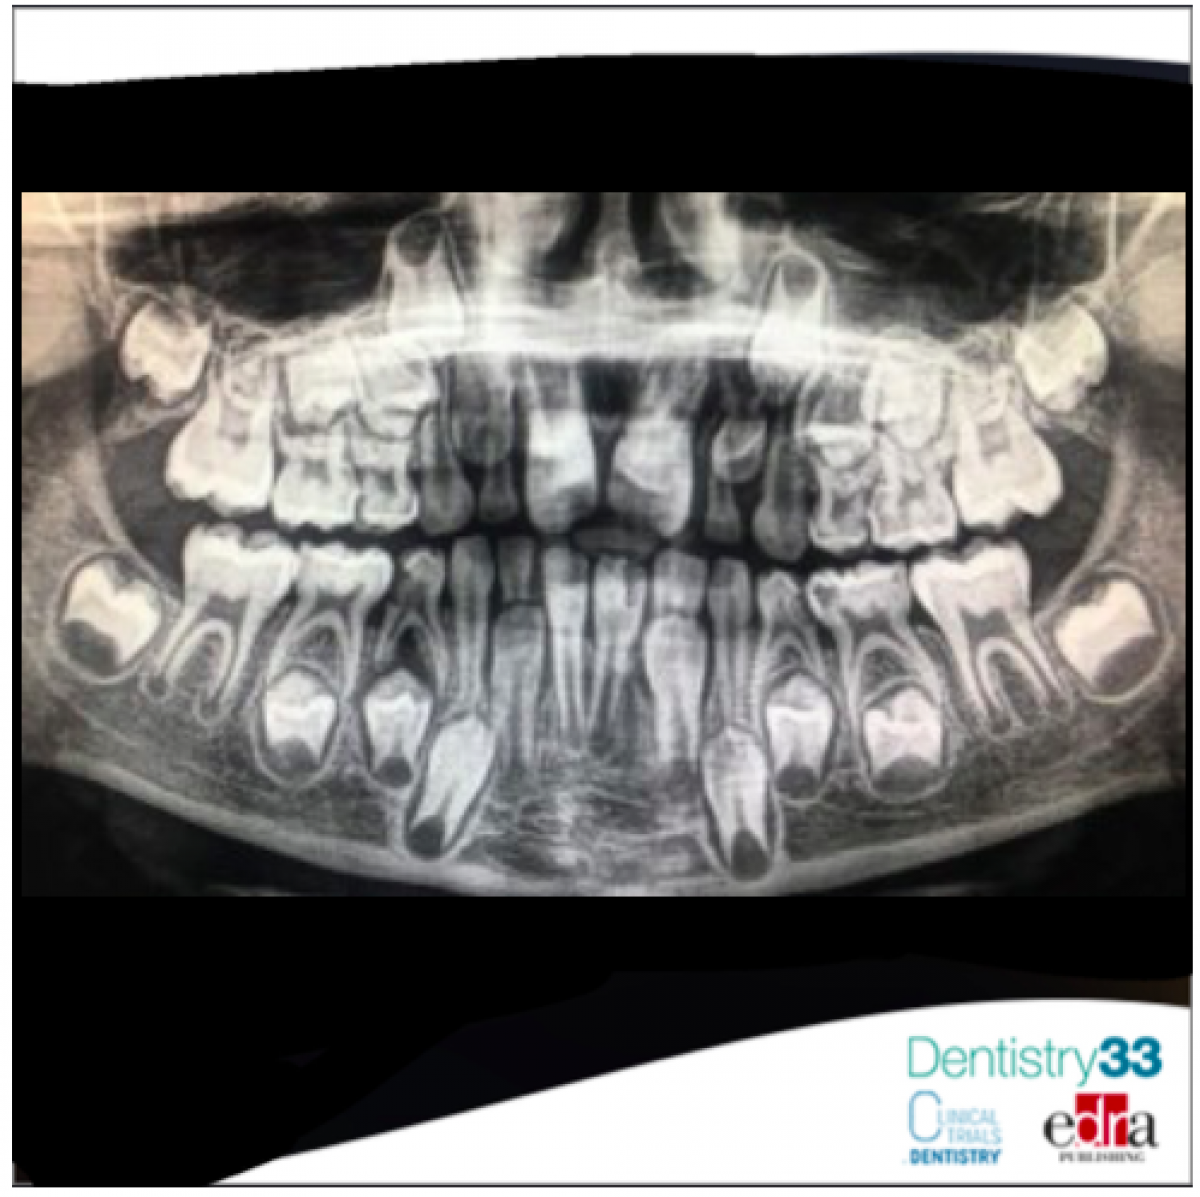

Antibiotic in pediatric dentistry: when prescription is necessary?